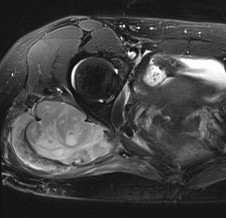

MRI

Sarcoma anterior thigh